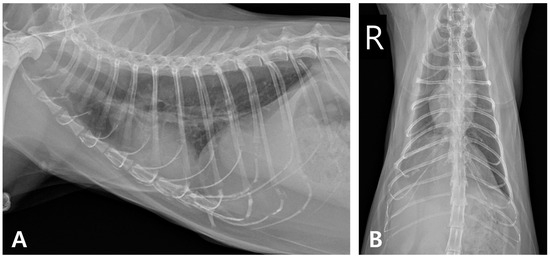

2. Case Description